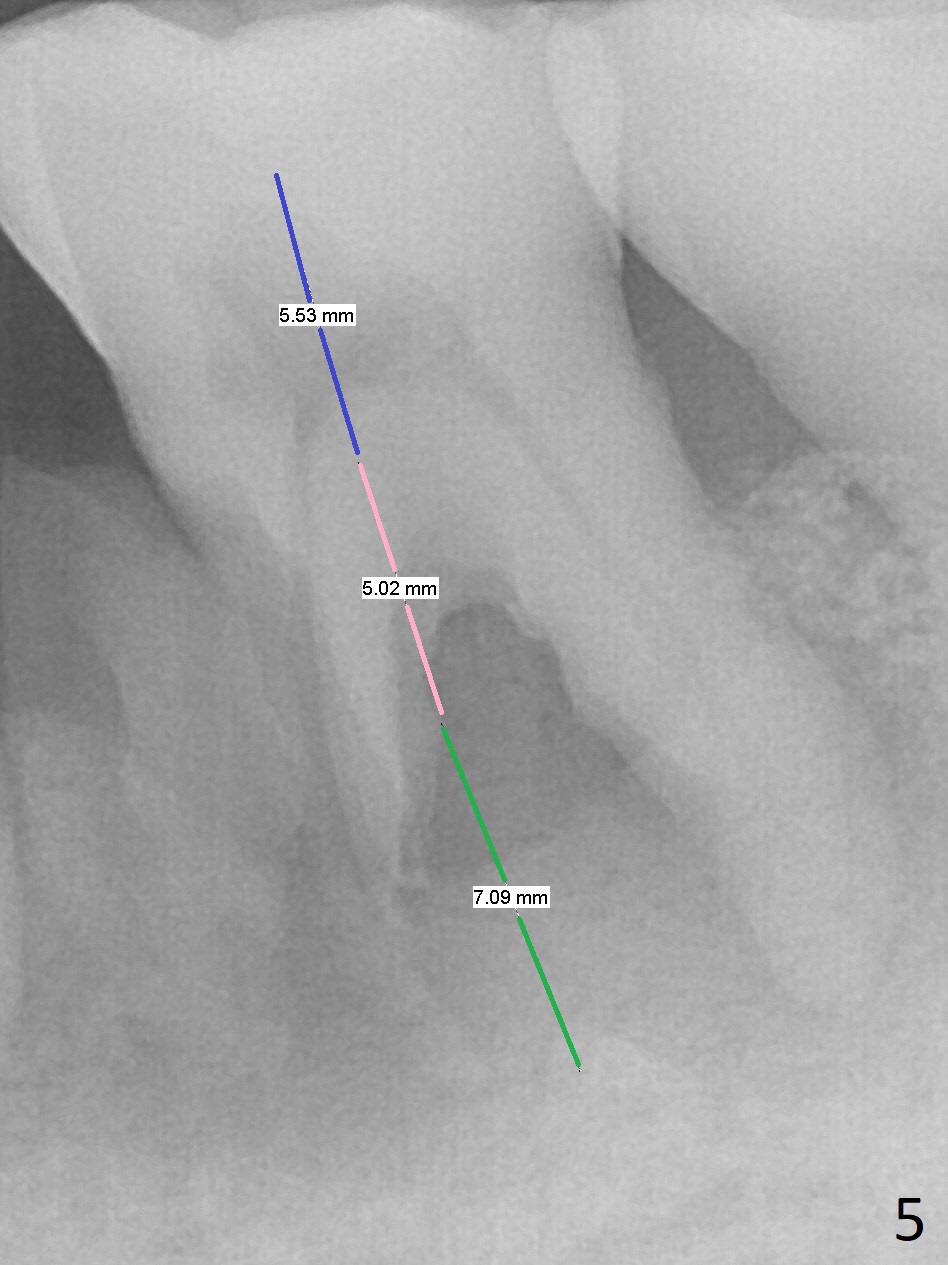

A 63-year-old man is a diabetic with history of good control. He masticates unilaterally with missing teeth #2,3 and 24 (Fig.1 (taken 5 years ago)). The latter has been restored with an implant. Last February the mesial root of the tooth #19 was found to have vertical fracture with bone loss until the base of the septum (Fig.2). The bone available for implantation is ~7-8 mm after root fracture (Fig.3,4). The initial osteotomy depth will be 7 mm (IS kit), followed by the calibrated parallel pin. The latter determines how many millimeters of an implant will be surrounded by the graft bone (Fig.4,5 (green: implant length; pink: cuff; blue: abutment length)). Since the buccal defect is severe with mesial root split (Fig.7 *), draw blood for PRF (2 large tubes). To save the remaining septum, place 2 of 1-piece implants on the either side of the septum (compare Fig.6,8). Take photos to compare buccal vs. lingual gingival recession. Tell the patient that the tooth #20 may be nonsalvageable. Since insurance preauthorization does not get approval for several times, the tooth #19 is extracted with socket preservation and periodontal dressing. The latter dislodges in 1 day. When the patient returns for follow up 4 days postop, the socket is exposed (Fig.9). An immediate implant should have been placed to keep the graft in place. PRF also helps. In fact preauthorization letter arrived 1 day earlier. It appears that guided surgery is indicated for limited bone height. The bone graft appears to gain ~ 5 mm bone in 4 months (Fig.10), which allows to place a 5x8.5 mm implant (Fig.11).